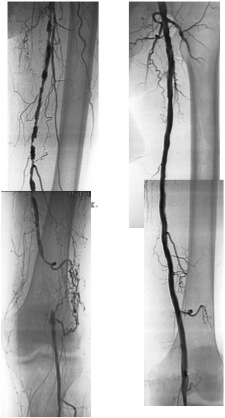

O tratamento endovascular consiste na dilatação dos segmentos estreitados ou mesmo ocluídos e pode ser complementado pelo implante de stents (malha metálica tubular), dependendo do caso. As vantagens deste método em relação à cirurgia aberta são: evitar incisões longas que podem complicar com isquemia das bordas e infecções, menor risco de lesão de estruturas adjacentes que são manipulados no acesso cirúrgico para confecção da ponte, menor tempo cirúrgico, possibilidade de realizar todo o procedimento com anestesia local evitando anestesia geral ou intradural prolongada, não necessidade de veia de calibre e comprimento adequado para servir de conduto arterial. O pós-operatório é significativamente mais confortável para o paciente já que a agressão cirúrgica e anestésica é consideravelmente menor e praticamente indolor em relação ao procedimento em si, podendo ser liberado para deambular no dia seguinte, dependendo das condições pré-operatórias de cada paciente.